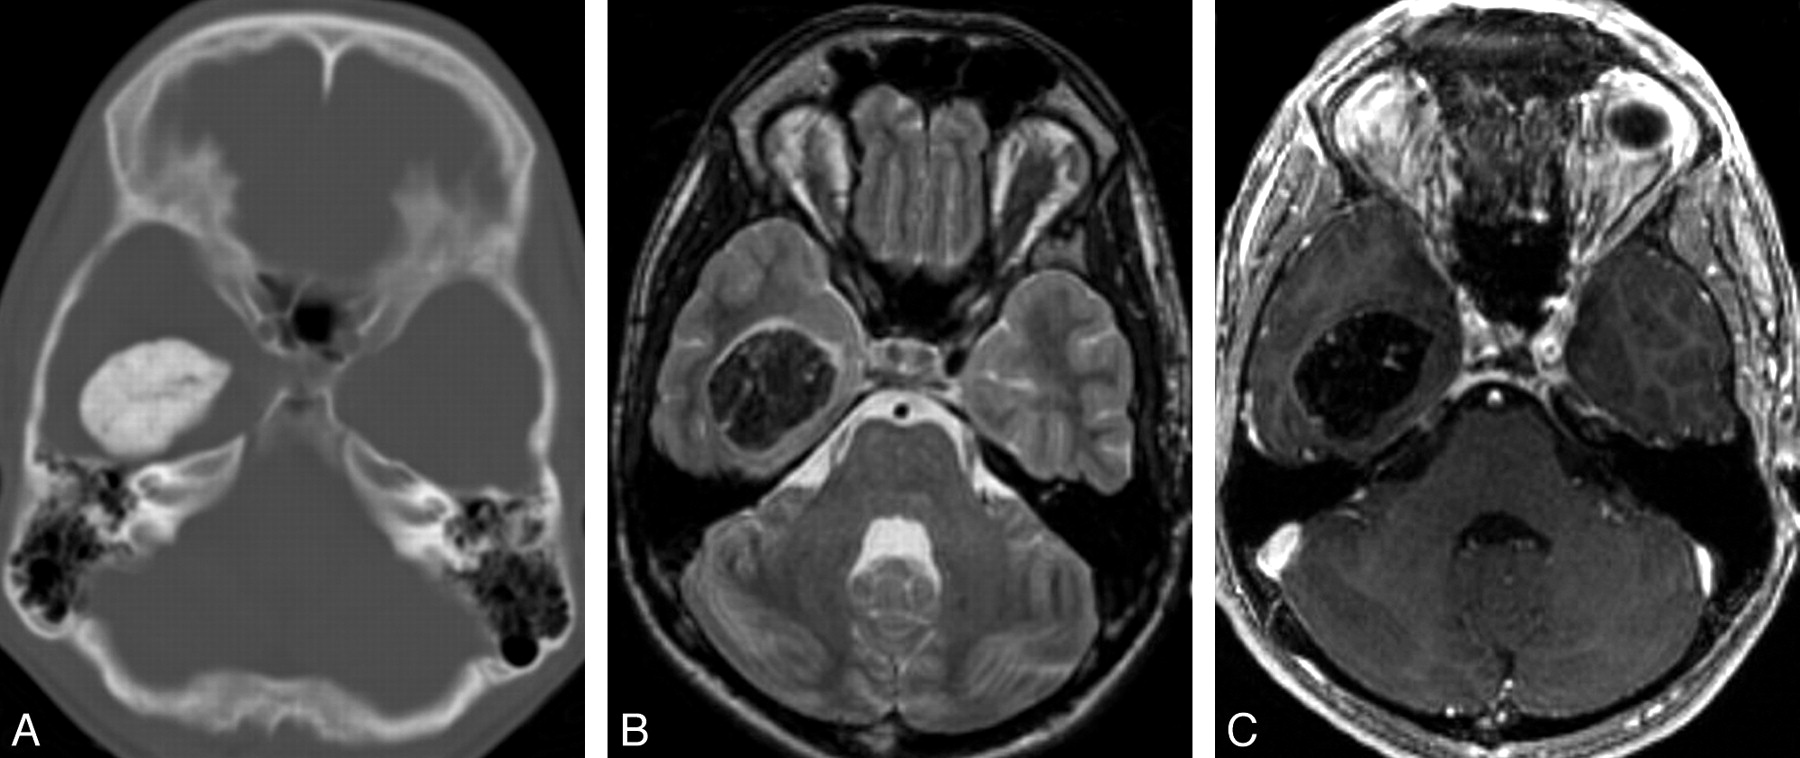

The first case, an incidentally found lesion, was a 3.2-cm extra-axial intraventricular mass (Figure 1). The remaining 3 patients with a history of seizures had intra-axial brain masses, ranging in size from 1 cm to 1.8 cm, located in the right parietal lobe near the postcentral gyrus, in the left hippocampus (Fig 2), and in the right temporal lobe, respectively. Preoperatively, the intra-axial temporal lobe lesions mimicked cavernous malformations or densely calcified neoplasms such as oligodendroglioma or ganglioglioma on the basis of their CT and MR imaging appearance. The intraventricular mass mimicked a meningioma but prospectively was thought to represent a pseudoneoplasm because of the lack of enhancement. The right parietal lesion had previously been resected 18 years previously, with a “benign” pathologic appearance and no specific diagnosis.

Typical radiologic features of intra-axial CAPNON. A, Noncontrast CT scan shows a left hippocampal mass with attenuated calcification. B, Coronal T2-weighted sequence demonstrates T2 hypointensity with a nodular border. C, Coronal T1-weighted sequence shows the typical T1 hypointensity. Preoperatively, this lesion was thought to represent a cavernous malformation. In retrospect, the nodular contour on T2 and lack of internal T2 hyperintensity would be atypical for a cavernous malformation of this size.

Important differential considerations for intra-axial calcified masses include calcifying neoplasms such as ganglioglioma and oligodendroglioma, vascular lesions such as cavernous malformation, and infections such as tuberculosis. Intraventricular masses can also raise the possibility of choroid plexus tumors, meningioma, or ependymal tumors. Our small series suggests that important MR imaging features may allow the radiologist to suggest CAPNON in the differential diagnosis. CT images of CAPNON typically show solid attenuated calcifications, and the MR imaging often shows a well-defined lesion that is uniformly hypointense on both T1- and T2-weighted images without surrounding edema. In our cases, only minimal linear internal or rim enhancement was present. The larger lesions (cases 1 and 2) best demonstrated the more serpiginous internal enhancement, which has been hypothesized to represent the vascular or stromal characteristic of these lesions (Fig 1).6 None of our cases demonstrated solid enhancement. However, an extra-axial mass presented by Shrier et al6 in the foramen magnum (Table 2) did show more solid enhancement, mimicking meningioma. None of our lesions showed significant surrounding edema. Our fourth case had surrounding T2 signal intensity, thought to represent gliosis from previous surgery, given the lack of mass effect. However, both cases presented by Shrier et al6 did have surrounding T2 prolongation thought to represent edema. Further investigation would be needed to identify the “typical” enhancement or pattern of edema in these rare lesions.

When considering the differential for calcifying intra-axial or extra-axial lesions, the uniform T1 and T2 hypointensity without solid enhancement is a key distinguishing feature. Calcified lesions with heterogeneous T2 signal intensity or T2 hyperintensity are more likely to be a calcified neoplasm and inconsistent with CAPNON. All of our cases and the previous 2 reported cases had uniform T2 hypointensity. Calcified lesions with the typical popcorn “T2 hyperintensity” and hemosiderin ring are more consistent with cavernous malformation and also distinguish themselves from CAPNON. Finally, the lack of solid enhancement helped to distinguish our intraventricular tumor from a meningioma or choroid plexus tumor.